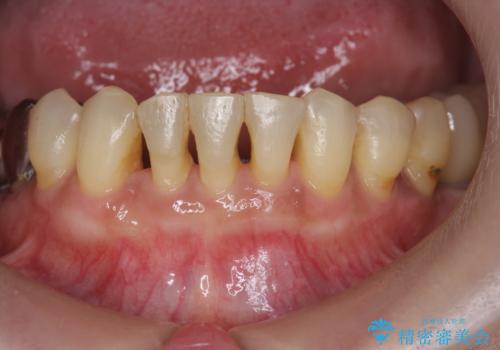

- 下顎前歯のグラつきがどんどん悪くなり、痛くて噛めなくなってきたことの改善を希望され来院されました。

下顎前歯の1本は前歯よりも前に出てしまい後ろからの力を受けることで、周囲の骨も吸収しグラつきも大きくみられます。

矯正治療を行うことで、歯を削ったり(ブリッジ)、手術の必要(インプラント)なく機能を欠損部位を無くし機能回復を達成することができました。